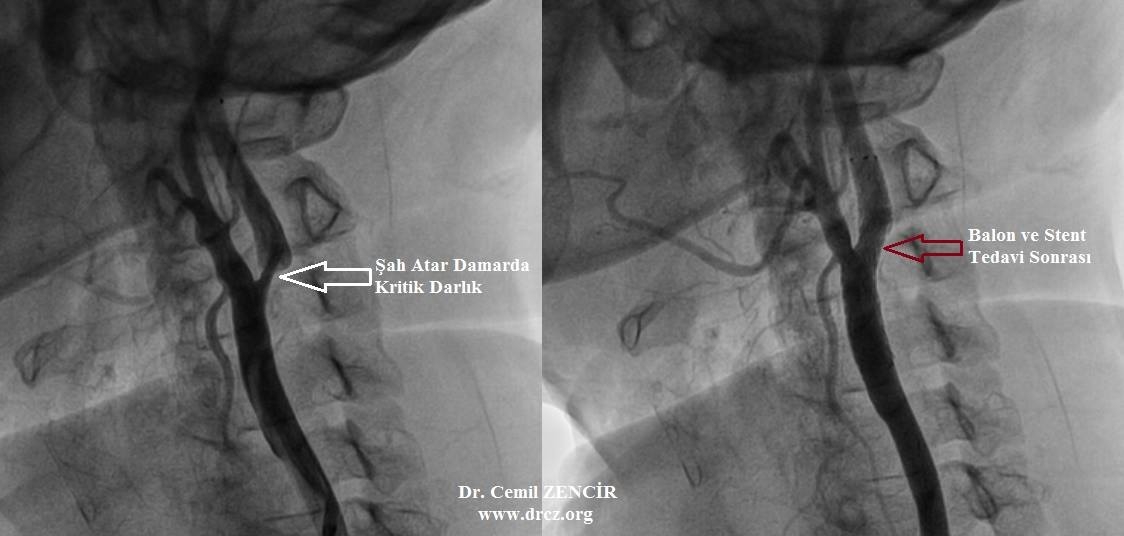

Darlığın derecesi ve hastanın şikayetinin var olup olmamasına bağlı olarak değişebilir. Kan sulandırıcı ilaç tedavisi, açık ameliyat veya stent uygulaması günümüzde uygulanan tedavi şekilleri olarak karşımıza çıkmaktadır.

Stent yerleştirildiği damarı açık tutmaya yarar. Şah damarının stentlenmesi beyine kan akımını normale getirir ve plak olan bölgeden pıhtı atmasını azaltarak inme riskini azaltır. Kasık damarından nadirende kol damarından girilir, damarın içine ilerletilen stent açılarak damar tıkanıklığı giderilmiş olur. Zamanla stent damar dokusu tarafından kaplanır, damara benzer bir hal alır.